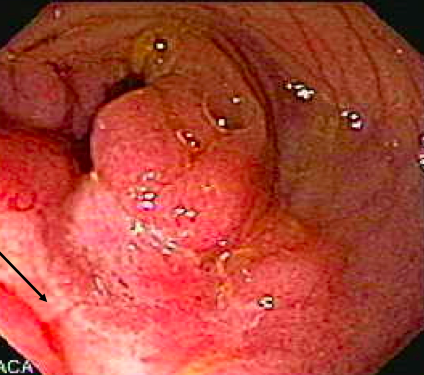

What is going on in these 2 images?

What are the endoscopic features of ulcerative colitis?

What do you see here?